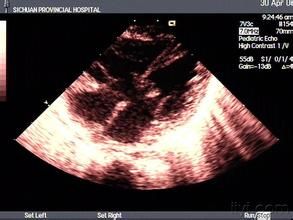

心電圖、胸片、超聲心動圖可明確診斷。右心導管檢查目前僅用於測定肺血管阻力,為判斷是否尚具有手術適應症提供依據。

1.房間隔或(和)室間隔回聲脫失的部位及大小。

2.觀察二、三尖瓣發育的狀況及瓣裂的程度,包括左右心房室瓣隔側瓣葉的附著關係,共同房室瓣形態及瓣下腱索所附著的部位。

3.房室腔內徑擴大的程度。

4.血流觀察心房與心室水平有無分流,分流方向、流速;房室瓣有無反流,反流束的方向與範圍,估測反流量。